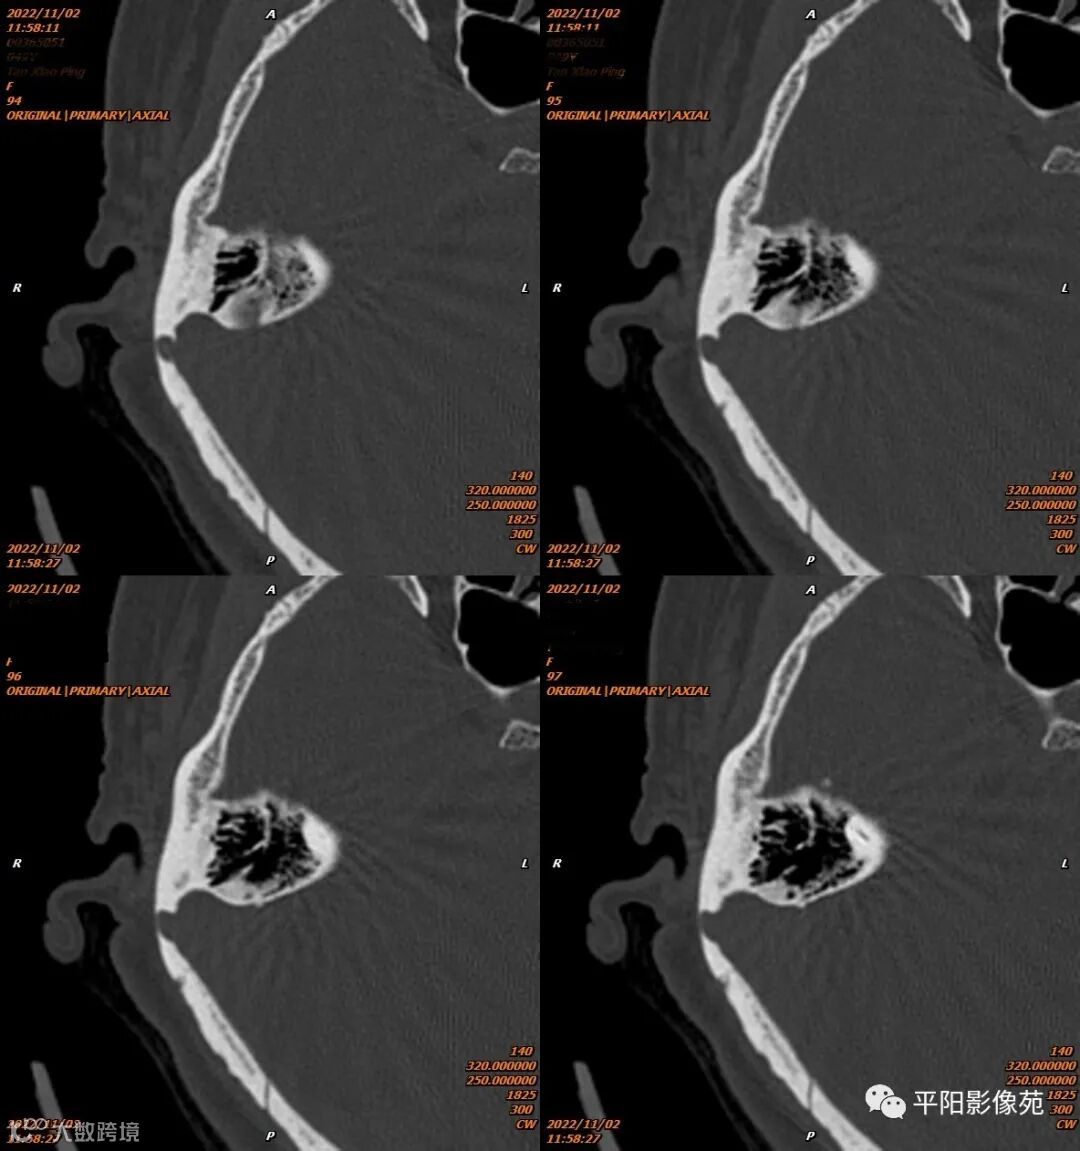

影像表现

影像表现:乙状窦局限性扩大,向右侧膨出,压迫右侧颞骨凹陷,前方乳突气房骨壁缺损。

影像诊断:乙状窦憩室